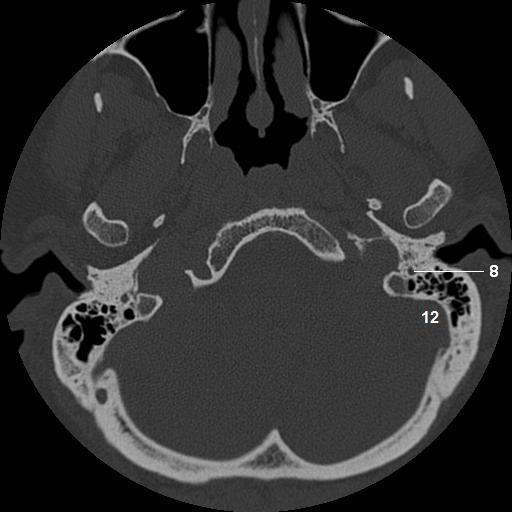

8.   descending facial nerve canal

12. sigmoid sinus